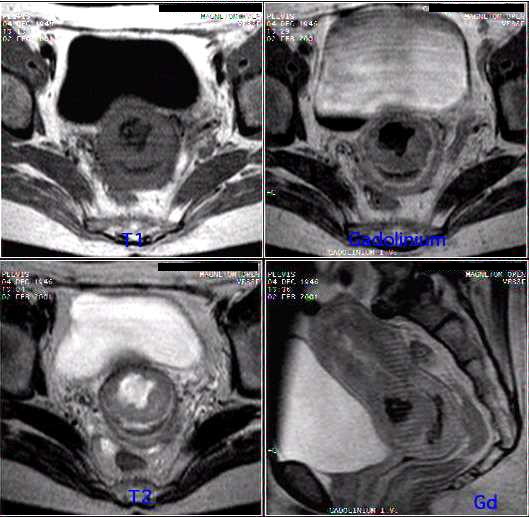

Musculosketal cases

Abdominal cases